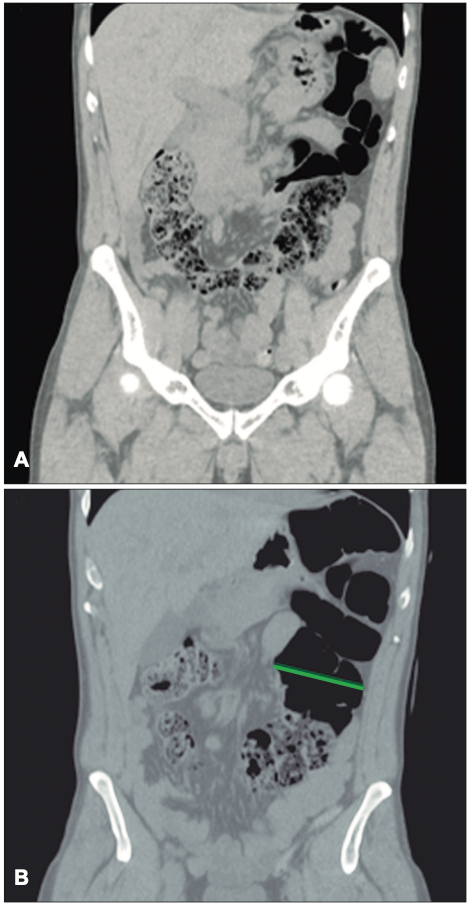

Posteriormente se realiza una tomografía computarizada de abdomen y pelvis sin contraste donde se observan asas intestinales dilatadas (Figura 1), ciego levemente distendido con abundante contenido propio, que cruza la línea media hacia el flanco izquierdo (Figuras 2 y 3), tracción e ingurgitación de los vasos mesentéricos (Figura 4).

Figura 3. Corte coronal. A: se observa ciego que cruza la línea media

para localizarse en el flanco izquierdo. B: ciego levemente distendido de aproximadamente 80

mm